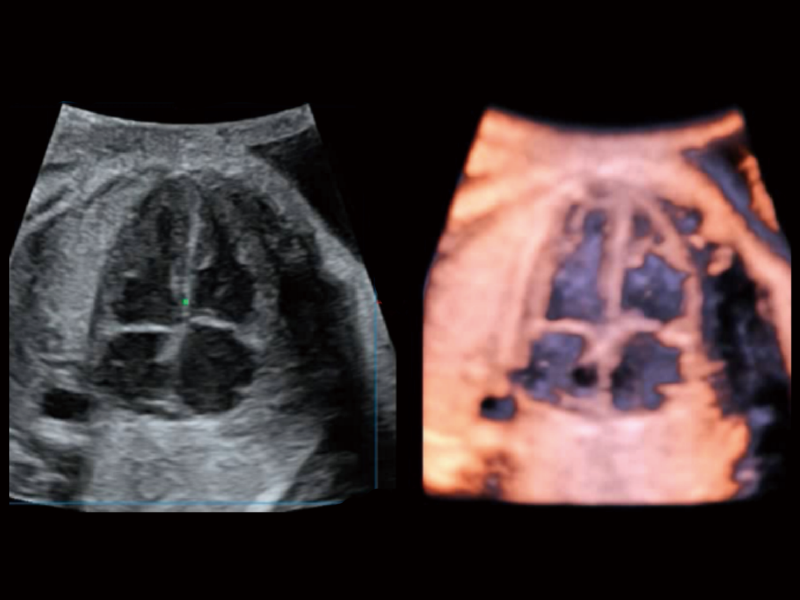

Exquisite Image Clarity & Hemodynamics

Image quality always lies at the core of definitive clinical outcomes. The P80 Elite introduces evolutional transducers with excellent 2D image clarity and color sensitivity for more confident assessment in anatomy and pathology.